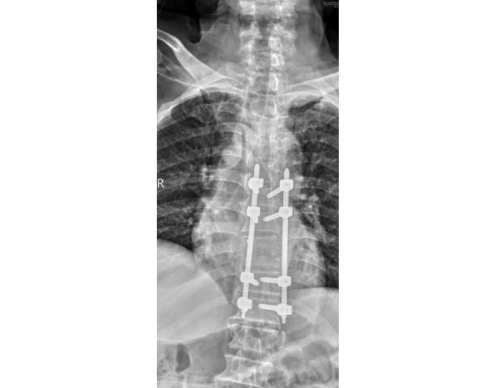

谭松入院后,经过相关检查后诊断为:“脊柱结核性截瘫(颈,胸,腰椎),胸椎多处骨质破坏,椎旁脓肿形成,肝肾功能不全、高血压、糖尿病、贫血、低蛋白血症、多处压疮”。患者的病情不容延误,脊柱二区曾浩主任迅速带领医护团队为其制定了个性化手术方案,邀请了麻醉科、心内科、内分泌科、输血科多学科会诊讨论,最终决定实施“胸椎后路结核病灶清除、椎管减压、椎间骨柱植骨融合、钉棒系统内固定术”。手术顺利,术后病情稳定,继续行抗结核治疗及营养支持、皮肤护理等对症治疗。

术后图